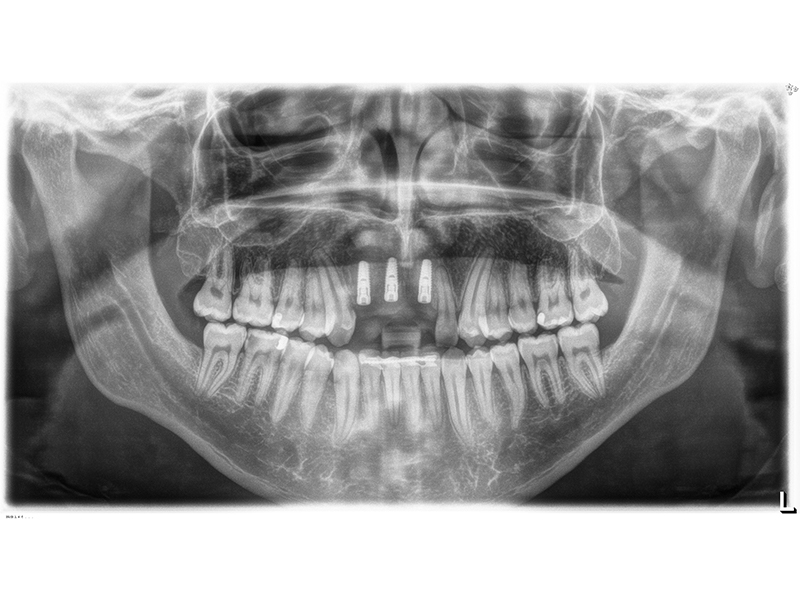

Unter dentalen Implantaten versteht man im allgemeinen eine Schraube, die dort, wo ein oder mehrere Zähne verloren gegangen sind, in den Kieferknochen "eingepflanzt" wird. Diese Therapieform der Implantologie hat sich in den letzten Jahren zu einem alltäglichen Therapieverfahren in der Zahnheilkunde entwickelt. Wissenschaftliche Untersuchungen zeigen hierfür eine Erfolgsquote von i. d. R. 80-98 % über 10 Jahre. Verglichen mit anderen zahnärztlichen Maßnahmen gibt es nahezu keine andere Therapie mit derart guten Erfolgsaussichten. Auch eine Verbesserung der Lebensqualität wird durch implantatgetragenen Zahnersatz laut klinischer Studien erreicht.